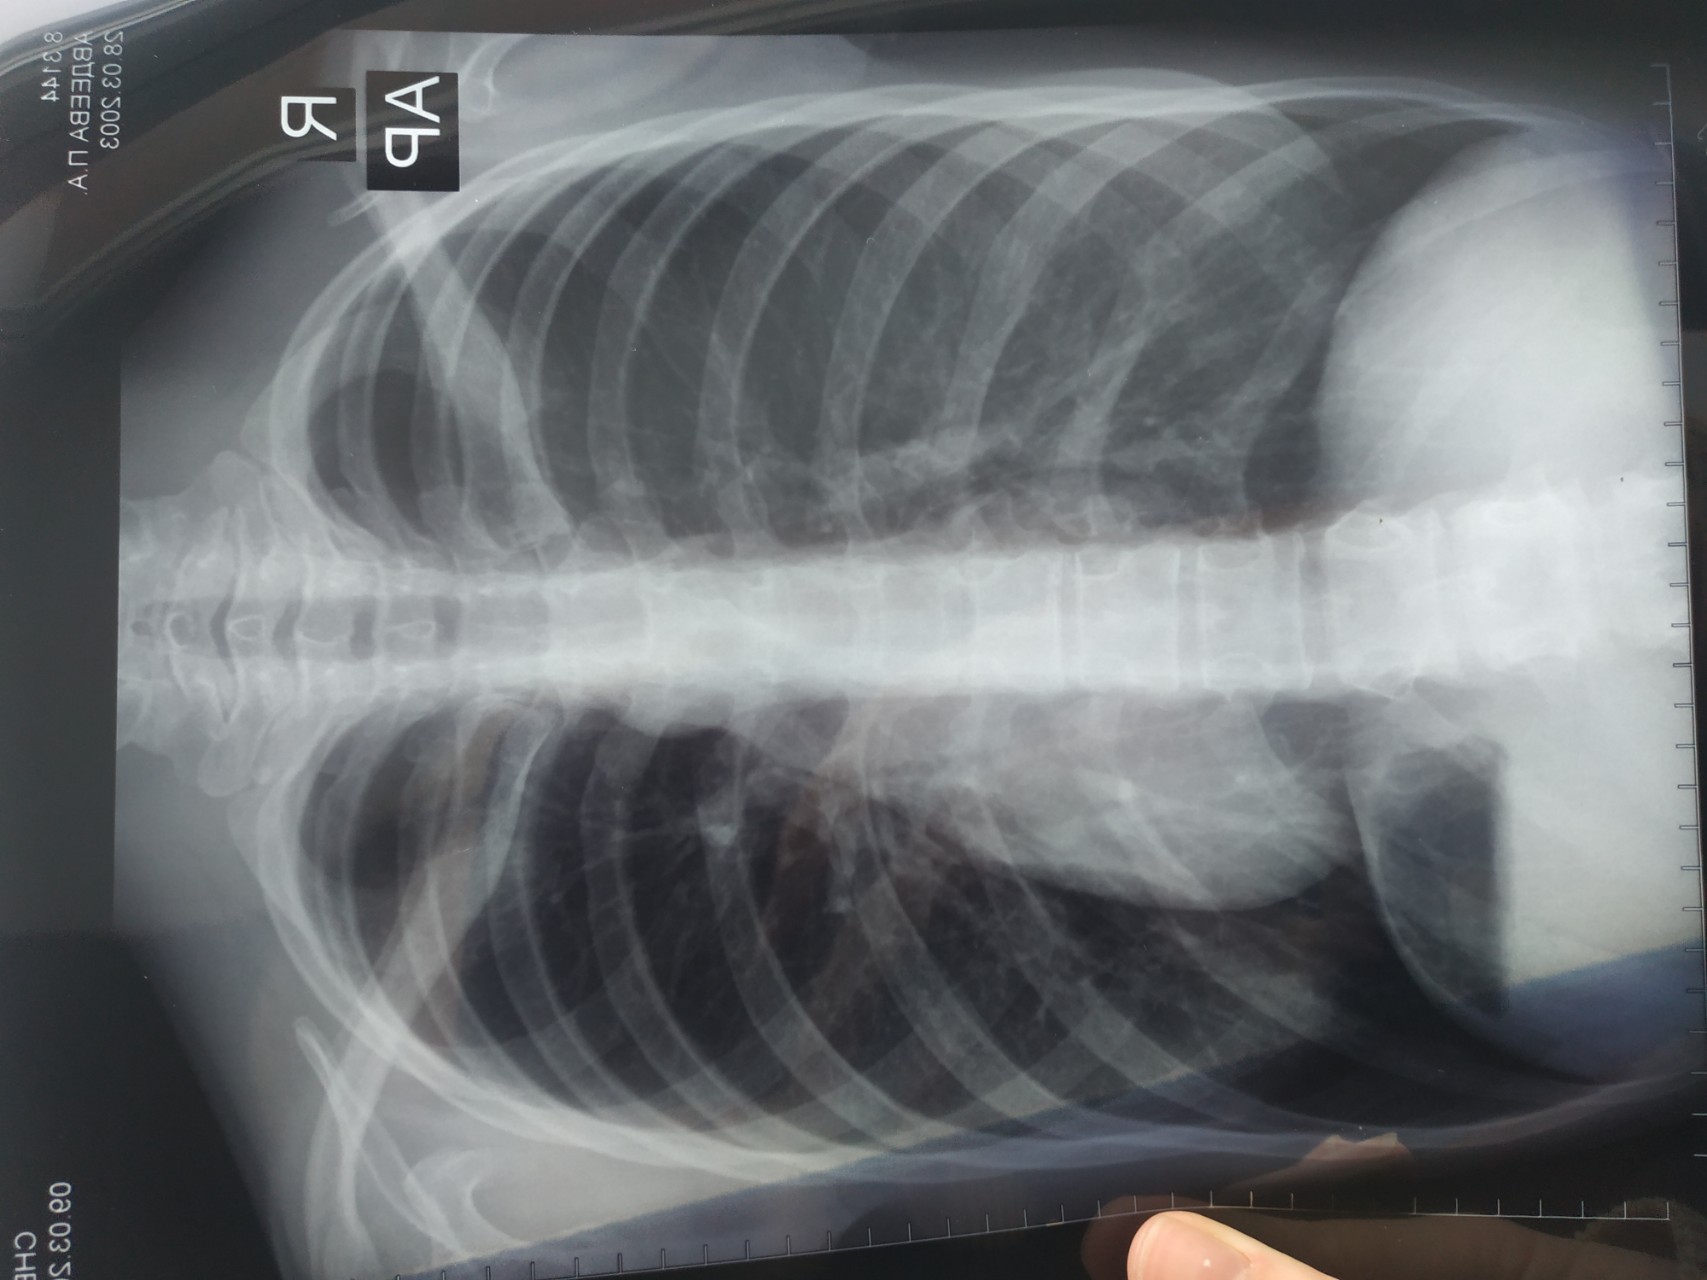

Нормальная рентгенограмма легких: что нужно знать

Раздел: Мудрость в объективе